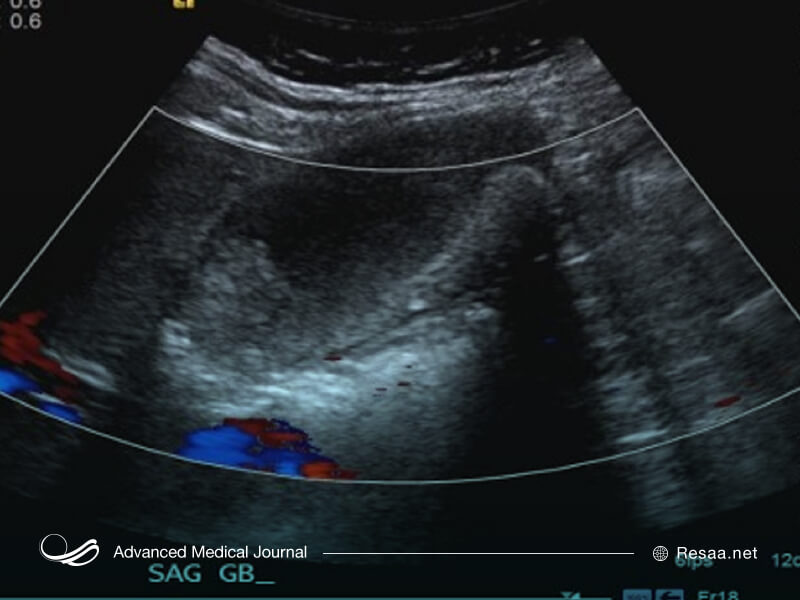

سونوگرافی، جهت تشخیص سرطان کیسه صفرا

سونوگرافی از امواج صوتی با فرکانس بالا برای تهیه تصاویر بخشهایی از بدن استفاده میکند. همچنین از سونوگرافی برای مشاهده کیسه صفرا و بررسی مشکلات یا سرطان در افراد مبتلا به درد شکم یا زردی استفاده میشود.

اغلب سونوگرافی شکمی اولین آزمایش تصویربرداری است، زمانی که پزشکان به سرطان کیسه صفرا مشکوک میشوند. این روش تأیید میکند که دیوار کیسه صفرا ضخیمتر از حد نرمال است. همچنین اطلاعاتی در مورد اندازه تومور در اختیار شما قرار میدهد.

همچنین از سونوگرافی برای دیدن اینکه آیا سرطان به کبد گسترش یافته است نیز استفاده میشود.